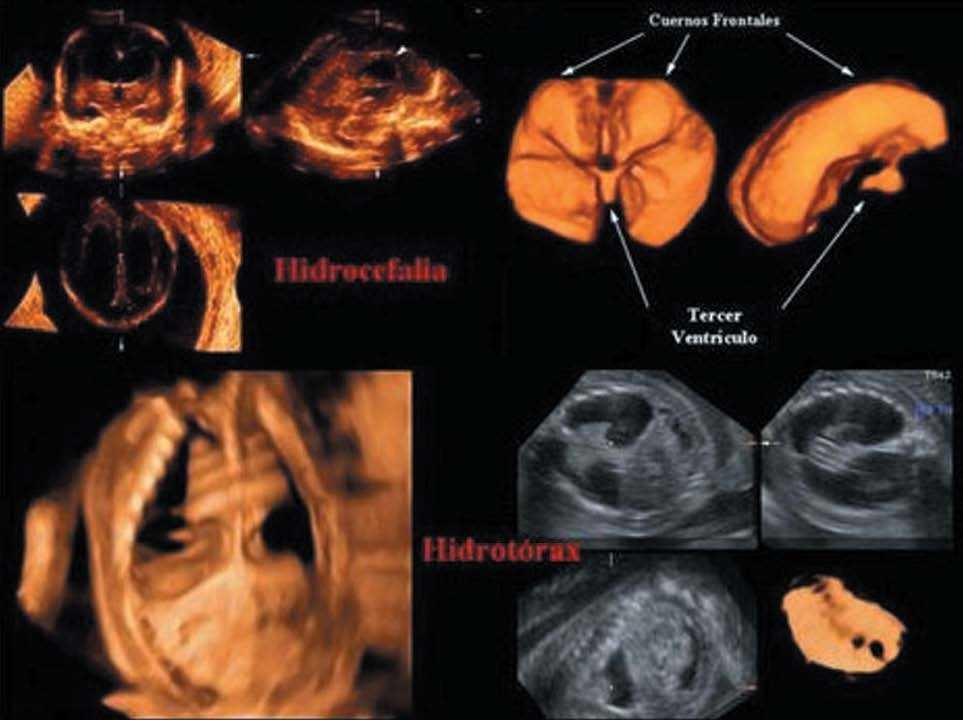

Se han aplicado recientemente para diagnosticar enfermedades fetales, especialmente combinando con el modo inverso, ya que así es posible visualizar las colecciones líquidas de cualquier etiología y observar su relación anatómica con los órganos adyacentes.

Se han realizado estudios4 sobre hidrocefalias, derrames pleurales (fig. 7), atresias duodenales y enfermedad renal (fig. 8).

Figura 7.El modo inverso muestra la dilatación bilateral de los ventrículos laterales. Un tercer ventrículo dilatado está presente con conexiones superiores hacia los ventrículos laterales a través del agujero de Monro. (Cedido gentilmente por W. Lee4.). Abajo se observa una colección pleural, y un hidrotórax que desplaza y comprime corazón. Se ven parcialmente 3 costillas y el corte del resto. El modo inverso muestra el área cardíaca desplazada y comprimida.